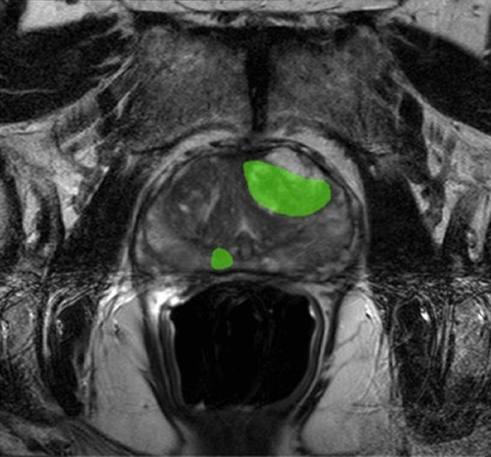

Complex MRI images contain vast information, but without expert labeling and segmentation, even the most advanced algorithms cannot learn effectively. Pareidolia Systems LLP, our annotation specialists combine medical expertise and advanced tools to deliver pixel-level accuracy in marking cancerous and non-cancerous regions. These annotations enable AI models to:

Traditional 2D medical imaging has its limits. With precise segmentation and 3D modeling, prostate cancer visualization becomes far more comprehensive. At Pareidolia, our advanced segmentation techniques allow for precise mapping of tumor boundaries, while our 3D modeling process converts these segmentations into realistic anatomical structures.